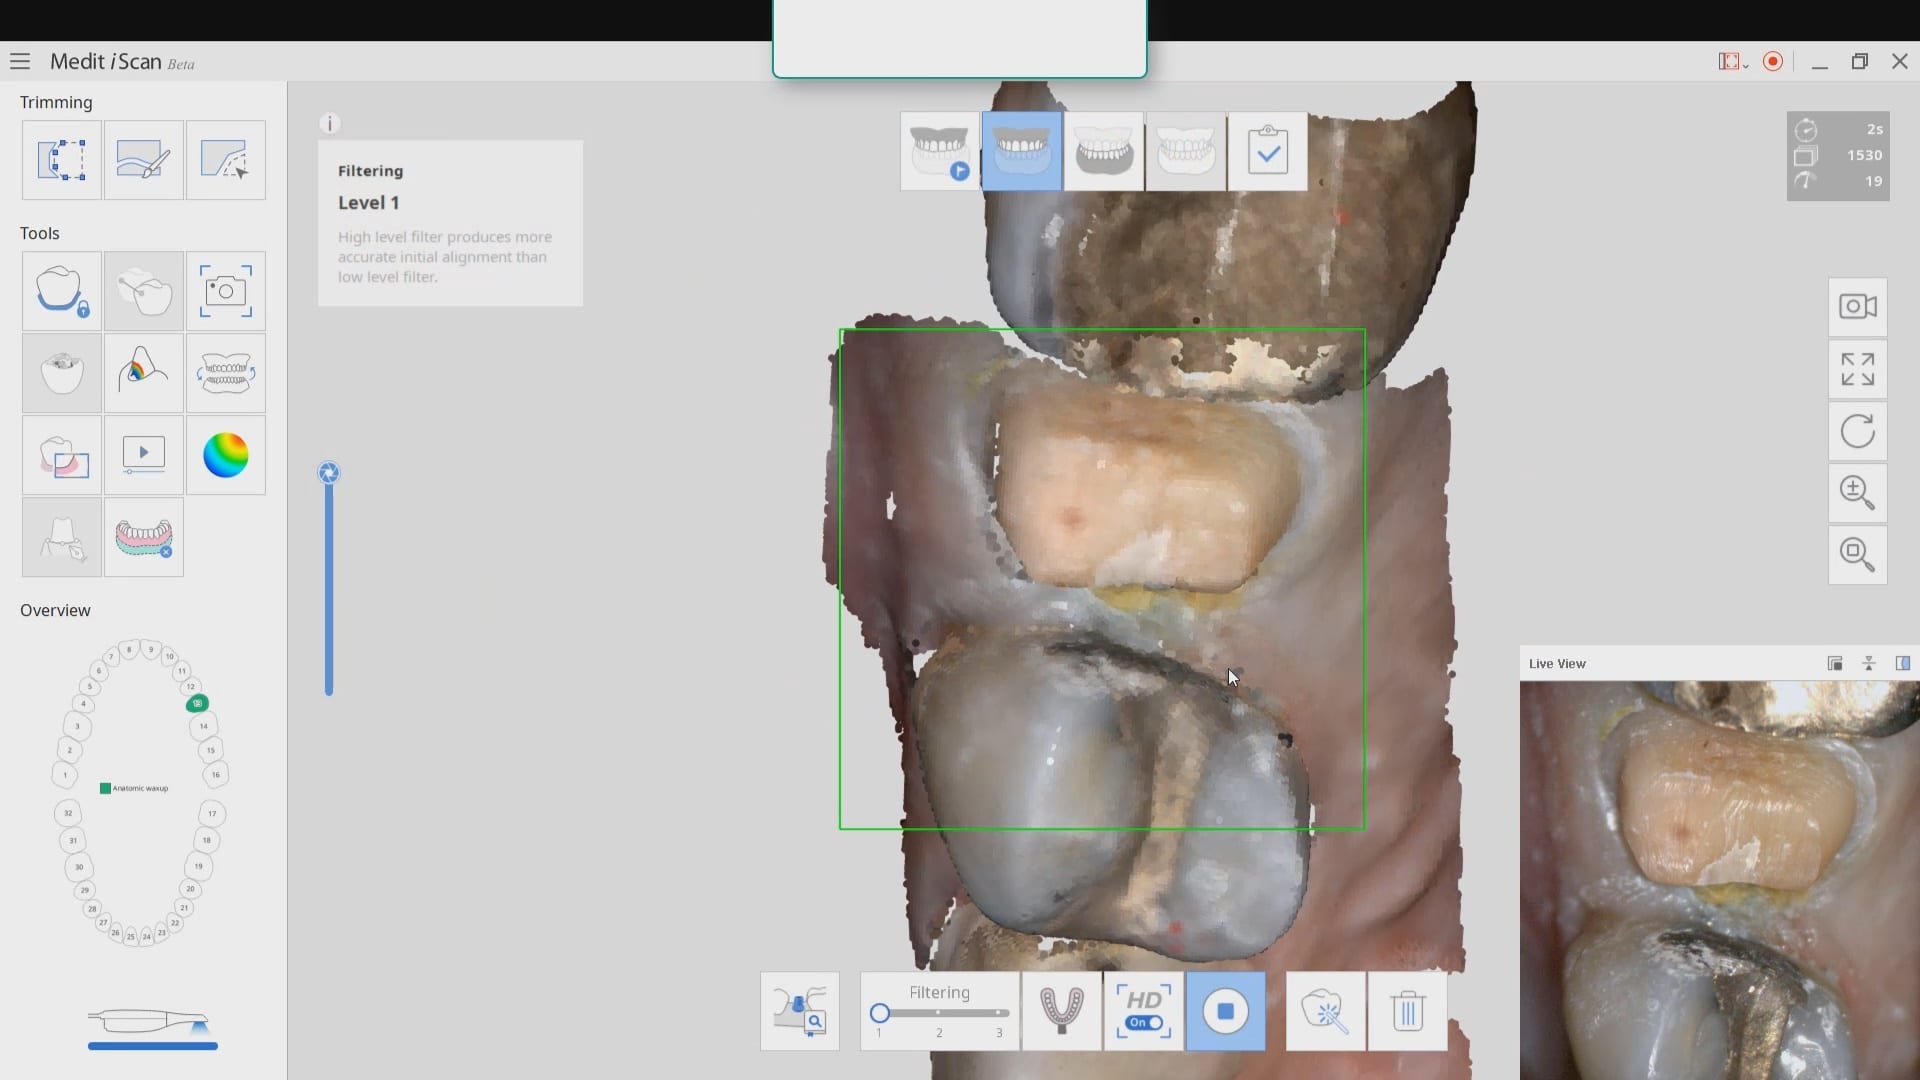

On September 5, 2019 Medit will officially launch the 2.1 software that will allow dentists to mark their own margins before sending to the lab. Since most images captured from […]